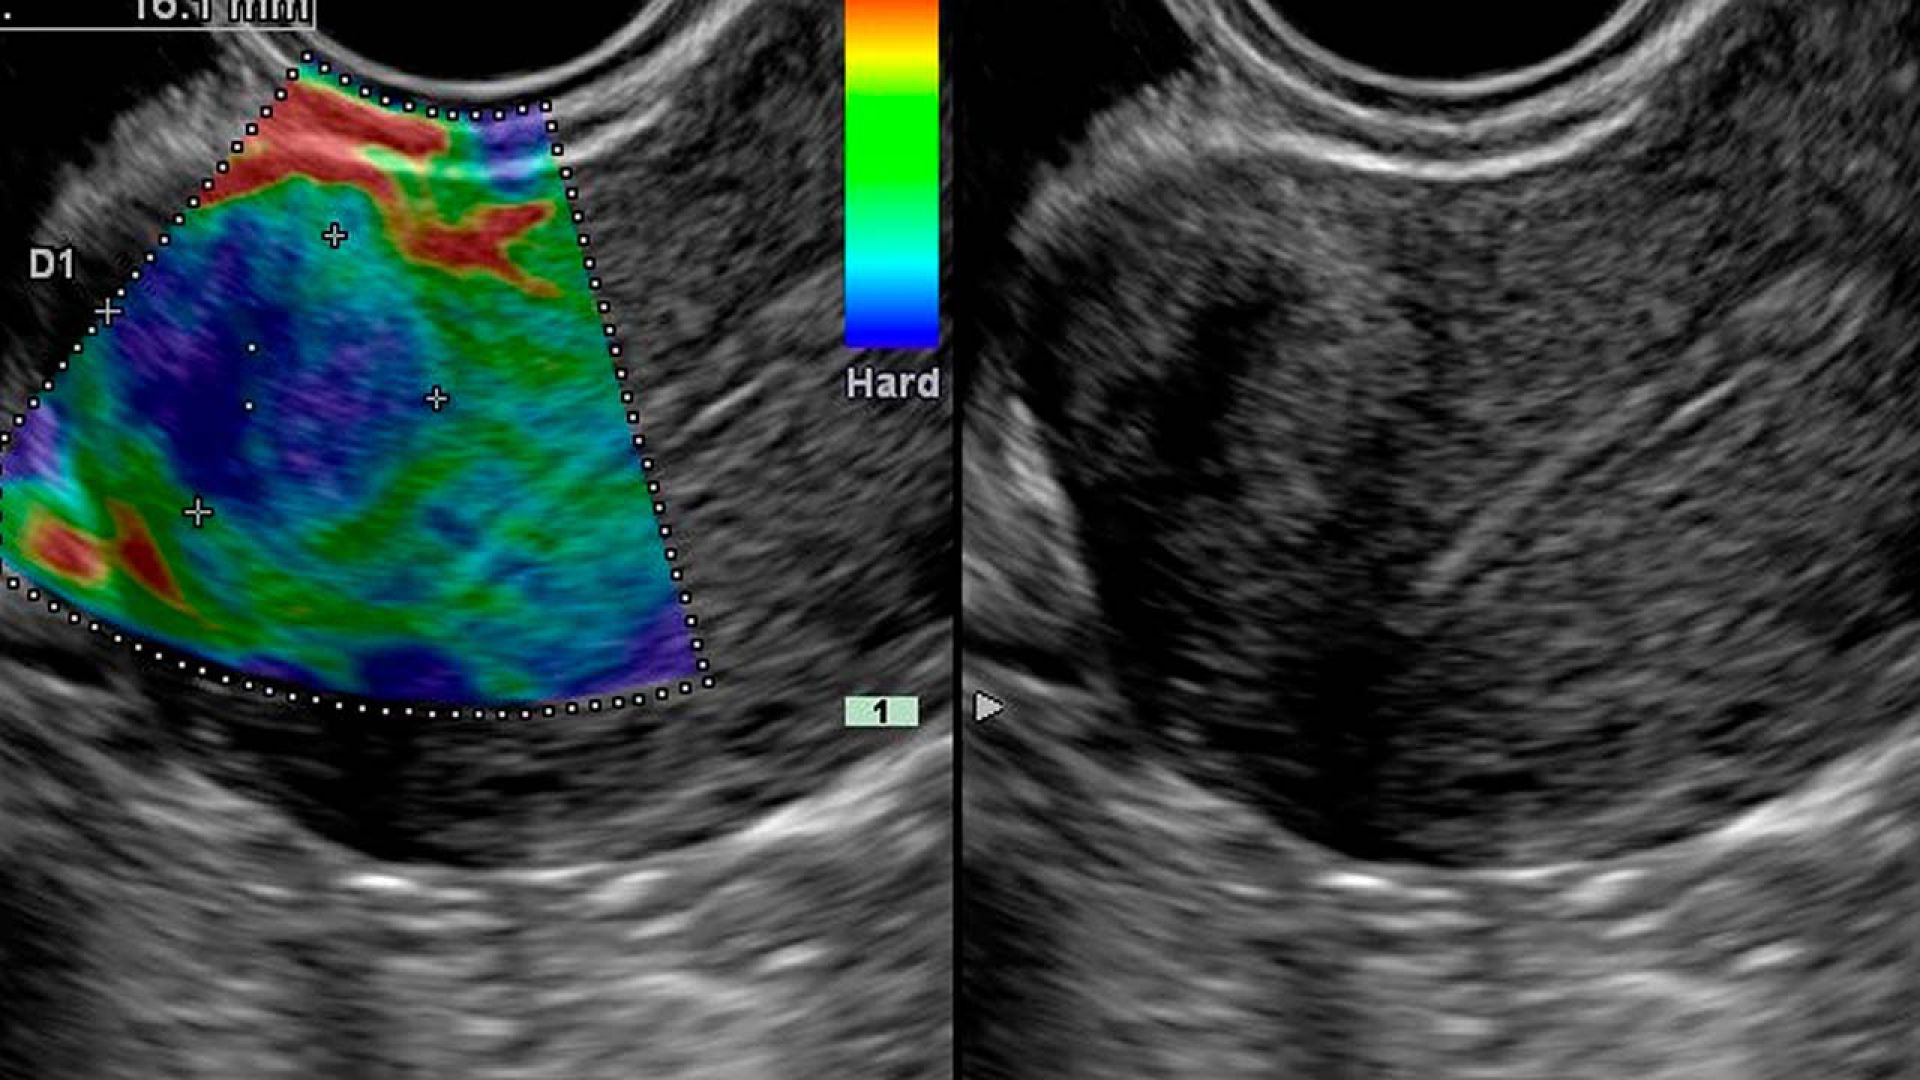

Выявление онкологии на ранних стадиях без биопсии на новом УЗИ-аппарате экспертного класса!

Метод применяется для диагностики различных органов и тканей:

• Молочные железы — определение типа новообразования, его структуры и агрессивности, контроль доброкачественных процессов.

• Щитовидная железа — диагностика новообразований, оценка их характера и состояния прилегающих лимфатических узлов.

• Мочеполовая система — обследование предстательной железы, мочеточников и семенных пузырьков у мужчин.

• Мягкие ткани, подкожно-жировая клетчатка, лимфатические узлы — обнаружение опухолей, уточнение их природы, местоположения и размеров.